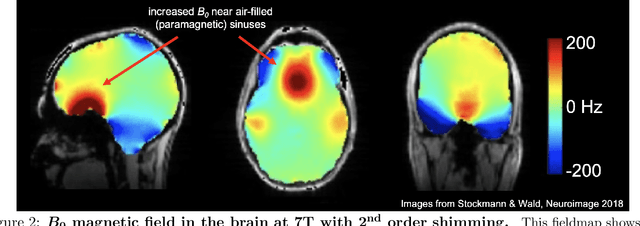

Abstract:In magnetic resonance imaging (MRI), inhomogeneity in the main magnetic field used for imaging, referred to as off-resonance, can lead to image artifacts ranging from mild to severe depending on the application. Off-resonance artifacts, such as signal loss, geometric distortions, and blurring, can compromise the clinical and scientific utility of MR images. In this review, we describe sources of off-resonance in MRI, how off-resonance affects images, and strategies to prevent and correct for off-resonance. Given recent advances and the great potential of low field and/or portable MRI, we also highlight the advantages and challenges of imaging at low field with respect to off-resonance.